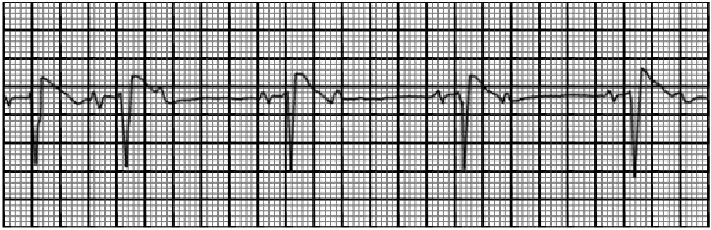

This rhythm strip shows sinus rhythm with blocked premature atrial complexes. The characteristic feature demonstrated here include

premature P waves which may have a different morphology from the sinus P waves and are not followed by a QRS complex. The PR interval of the sinus beats remains constant. The early atrial complex reaches the A-V junction before repolarization has been completed and is not conducted.